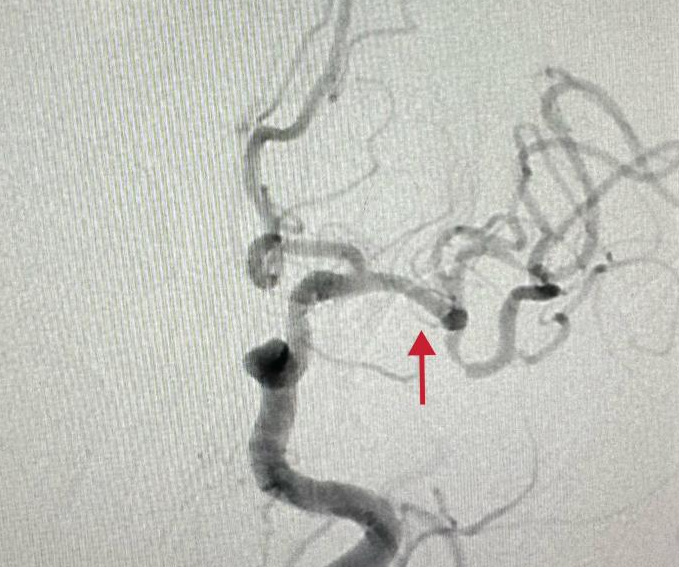

为确保清除“肇事血管”隐患,经老人家属许可,主任王万铭及团队成员谭建军等此举中医护,为桂奶奶施行了血管造影。检查确认了原诊断为真,桂奶奶左侧大脑中动脉已发生闭塞。遇到老年患者血管复杂迂回难题,医者不畏挑战,持续努力,最终成功将取栓导管送达闭塞处,展开支架释放,并成功取出一约一厘米的暗红色血栓。

手术每一步均蕴藏着重重考验,医师须精确施术,以防损伤毗邻血管与组织。他们指法稳健,目不斜视,每项细致操作均关乎桂奶奶的生命安全。历经紧张有序的手术历程,医师们最终成功摘除血栓,恢复血管通畅。